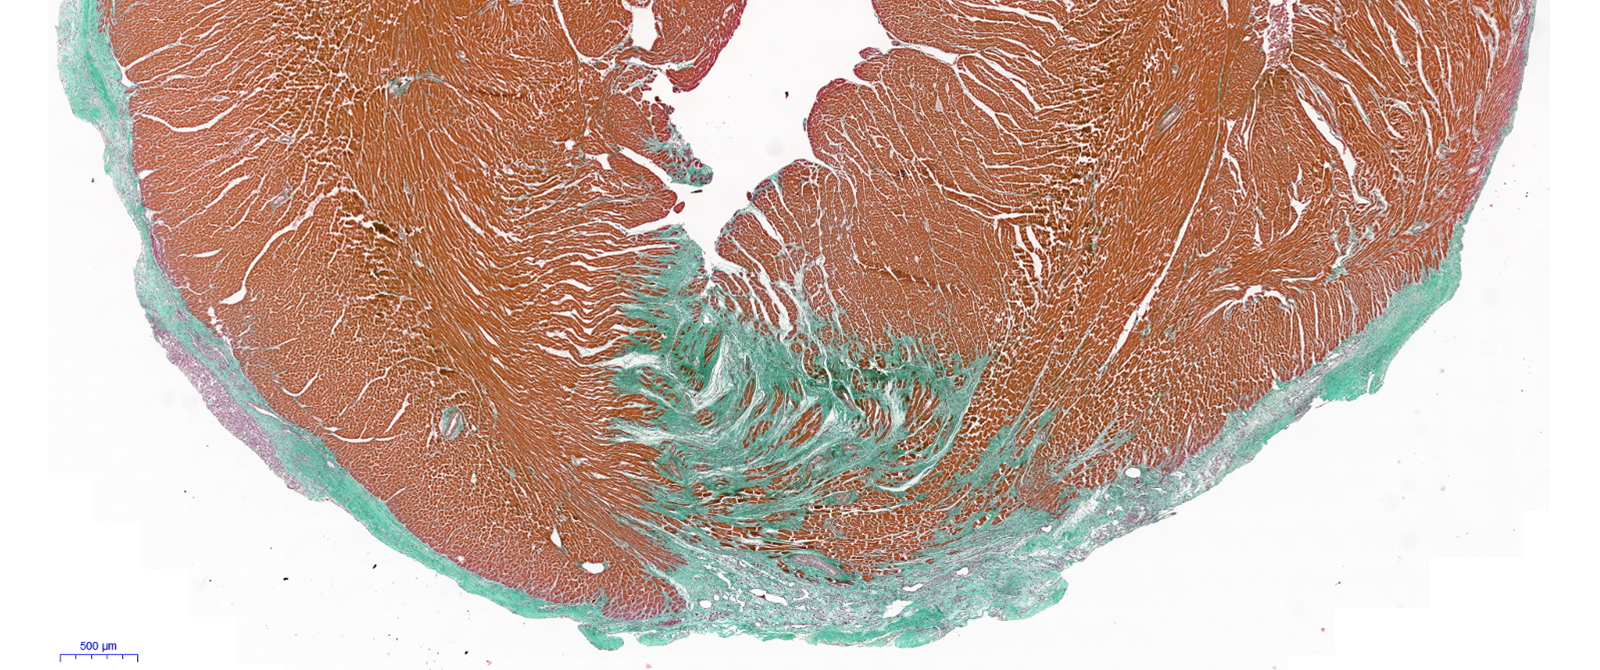

• Identification of a bandage for cardiac regeneration

In pathophysiologic conditions, the adult heart has a low regenerative capacity. We are developing a biological bandage for the treatment of the damaged myocardium. The biological bandage is composed of a matrix and cells. The therapeutic biological bandage secretes cytokines, interleukins, growth factors, exosomes that trigger the immune system, and stimulate the in-situ repair mechanisms. The biological bandage should stimulate regeneration of the damaged tissue by a functional tissue.